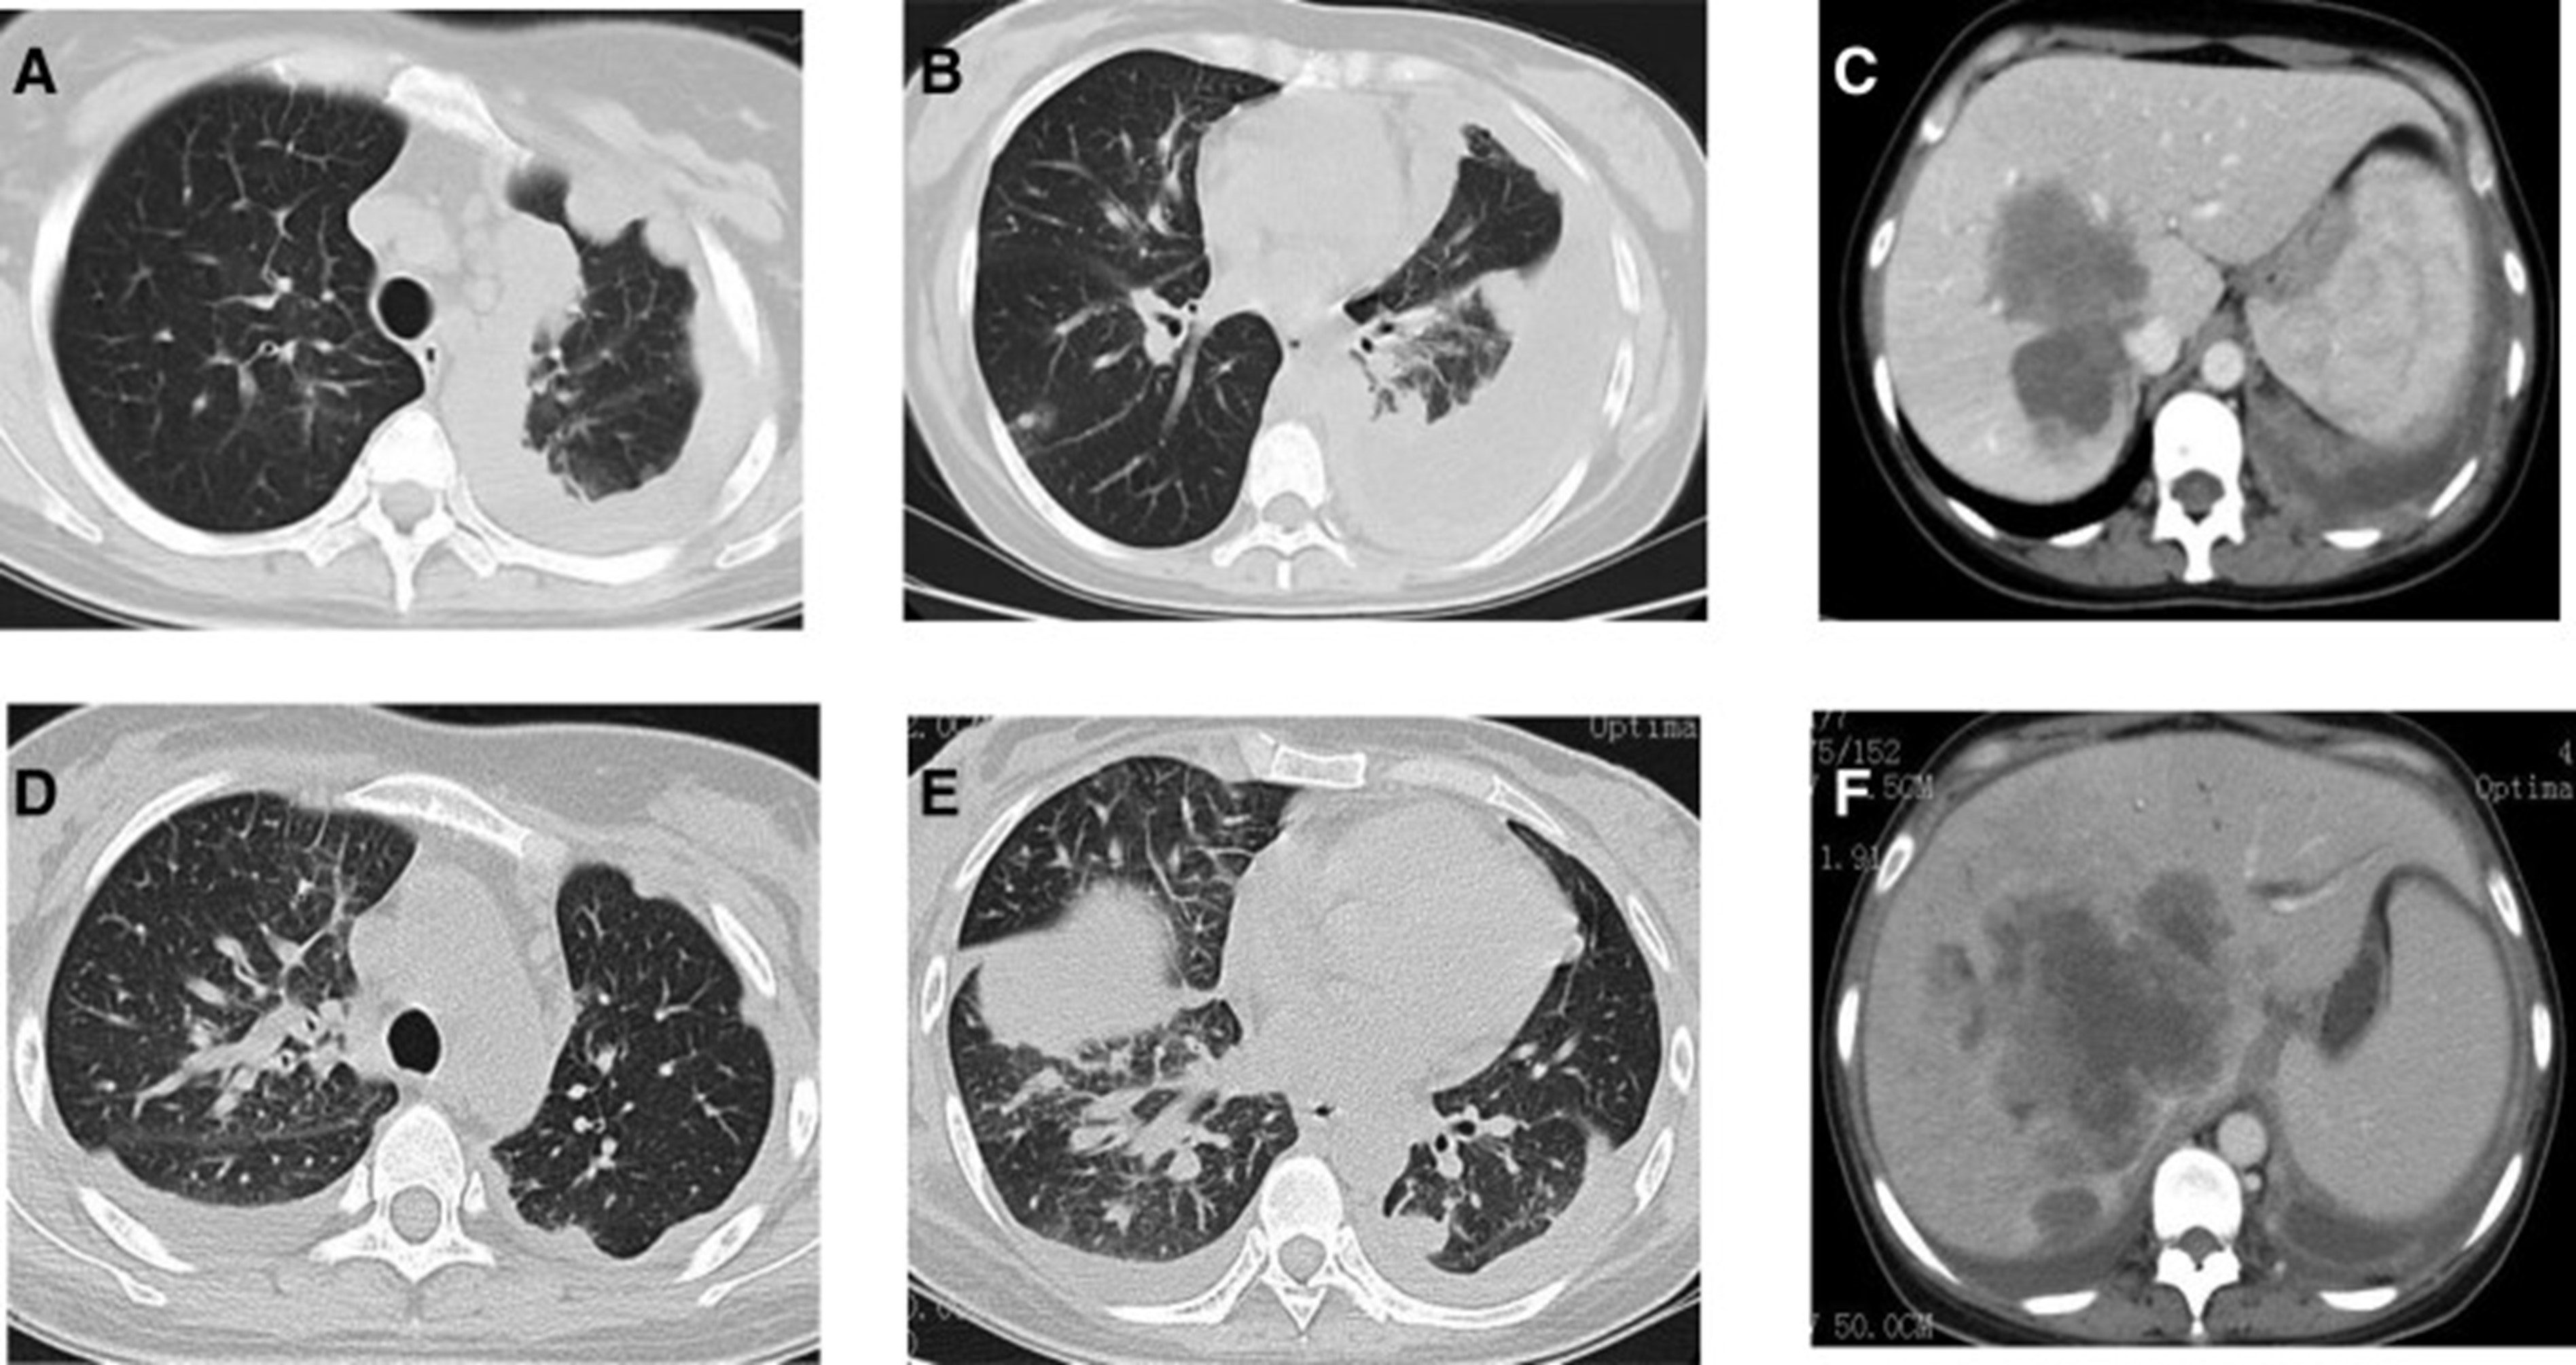

2020年4月,患者胸部CT示“双肺多发结节,纵隔及肺门多发肿大淋巴结;附着于肝右叶,略呈低密度肿块影”(图 1)。(图4A,4A、B)和腹部CT显示“肝脏多发肿块”(图1)。(图 4C)。骨扫描显示“身体多个部位的骨代谢异常增强”。2020年4月19日,对“右肝肿块和右锁骨上肿块”进行活检,病理指征(右肝肿块抽吸、右锁骨上肿块抽吸)为低分化腺癌。结合免疫组化结果,首先考虑的是肺腺癌转移。最终诊断为“IV期肺腺癌伴多发肝和骨转移”。基因检测显示“EML 4-ALK 融合,PD-L1 肿瘤阳性细胞数TPS 80%”(图 2)。(图1和和2)。

和 2020 年 6 月 (D-F).jpg)

图 4:2020 年 4 月 (A-C) 和 2020 年 6 月 (D-F) 的 CT 扫描。CT = 计算机断层扫描。

2020年5月1日,患者开始口服艾乐替尼靶向药物进行治疗,2020年6月25日复查,确定治疗效果为PR(部分有效)(根据RECIST1.1)显示肺病灶和肝转移灶明显减少(图1)。(图 3D-F)。2020 年 8 月 27 日复查确定治疗效果为疾病进展(PD, progressive disease),根据 RECIST1.1显示肝脏病变变大(图 1)(图 4A-D)。进行了第二次肝活检,随后的病理学显示“(肝)低分化癌,结合免疫组织化学分析考虑肺腺癌转移”。组织活检进行了第二轮基因检测,结果显示“BRAFV600E 14.79%,EML 4-ALK fusion 14.47%”(图 1)(图 5)。2020年9月20日,对患者我以为用恩沙替尼联合达拉非尼靶向治疗。治疗开始后,患者出现明显发热、寒战、乏力和厌食。期间患者左侧出现大量胸腔积液,胸腔积液中脱落细胞为“非典型细胞,考虑为腺癌”。随后,该患者接受了 1 次胸腔内铂输注。

和 2020 年 8 月.jpg)

图 5:2020 年 6 月(A 和 B)和 2020 年 8 月(C 和 D)的 CT 扫描。CT = 计算机断层扫描。